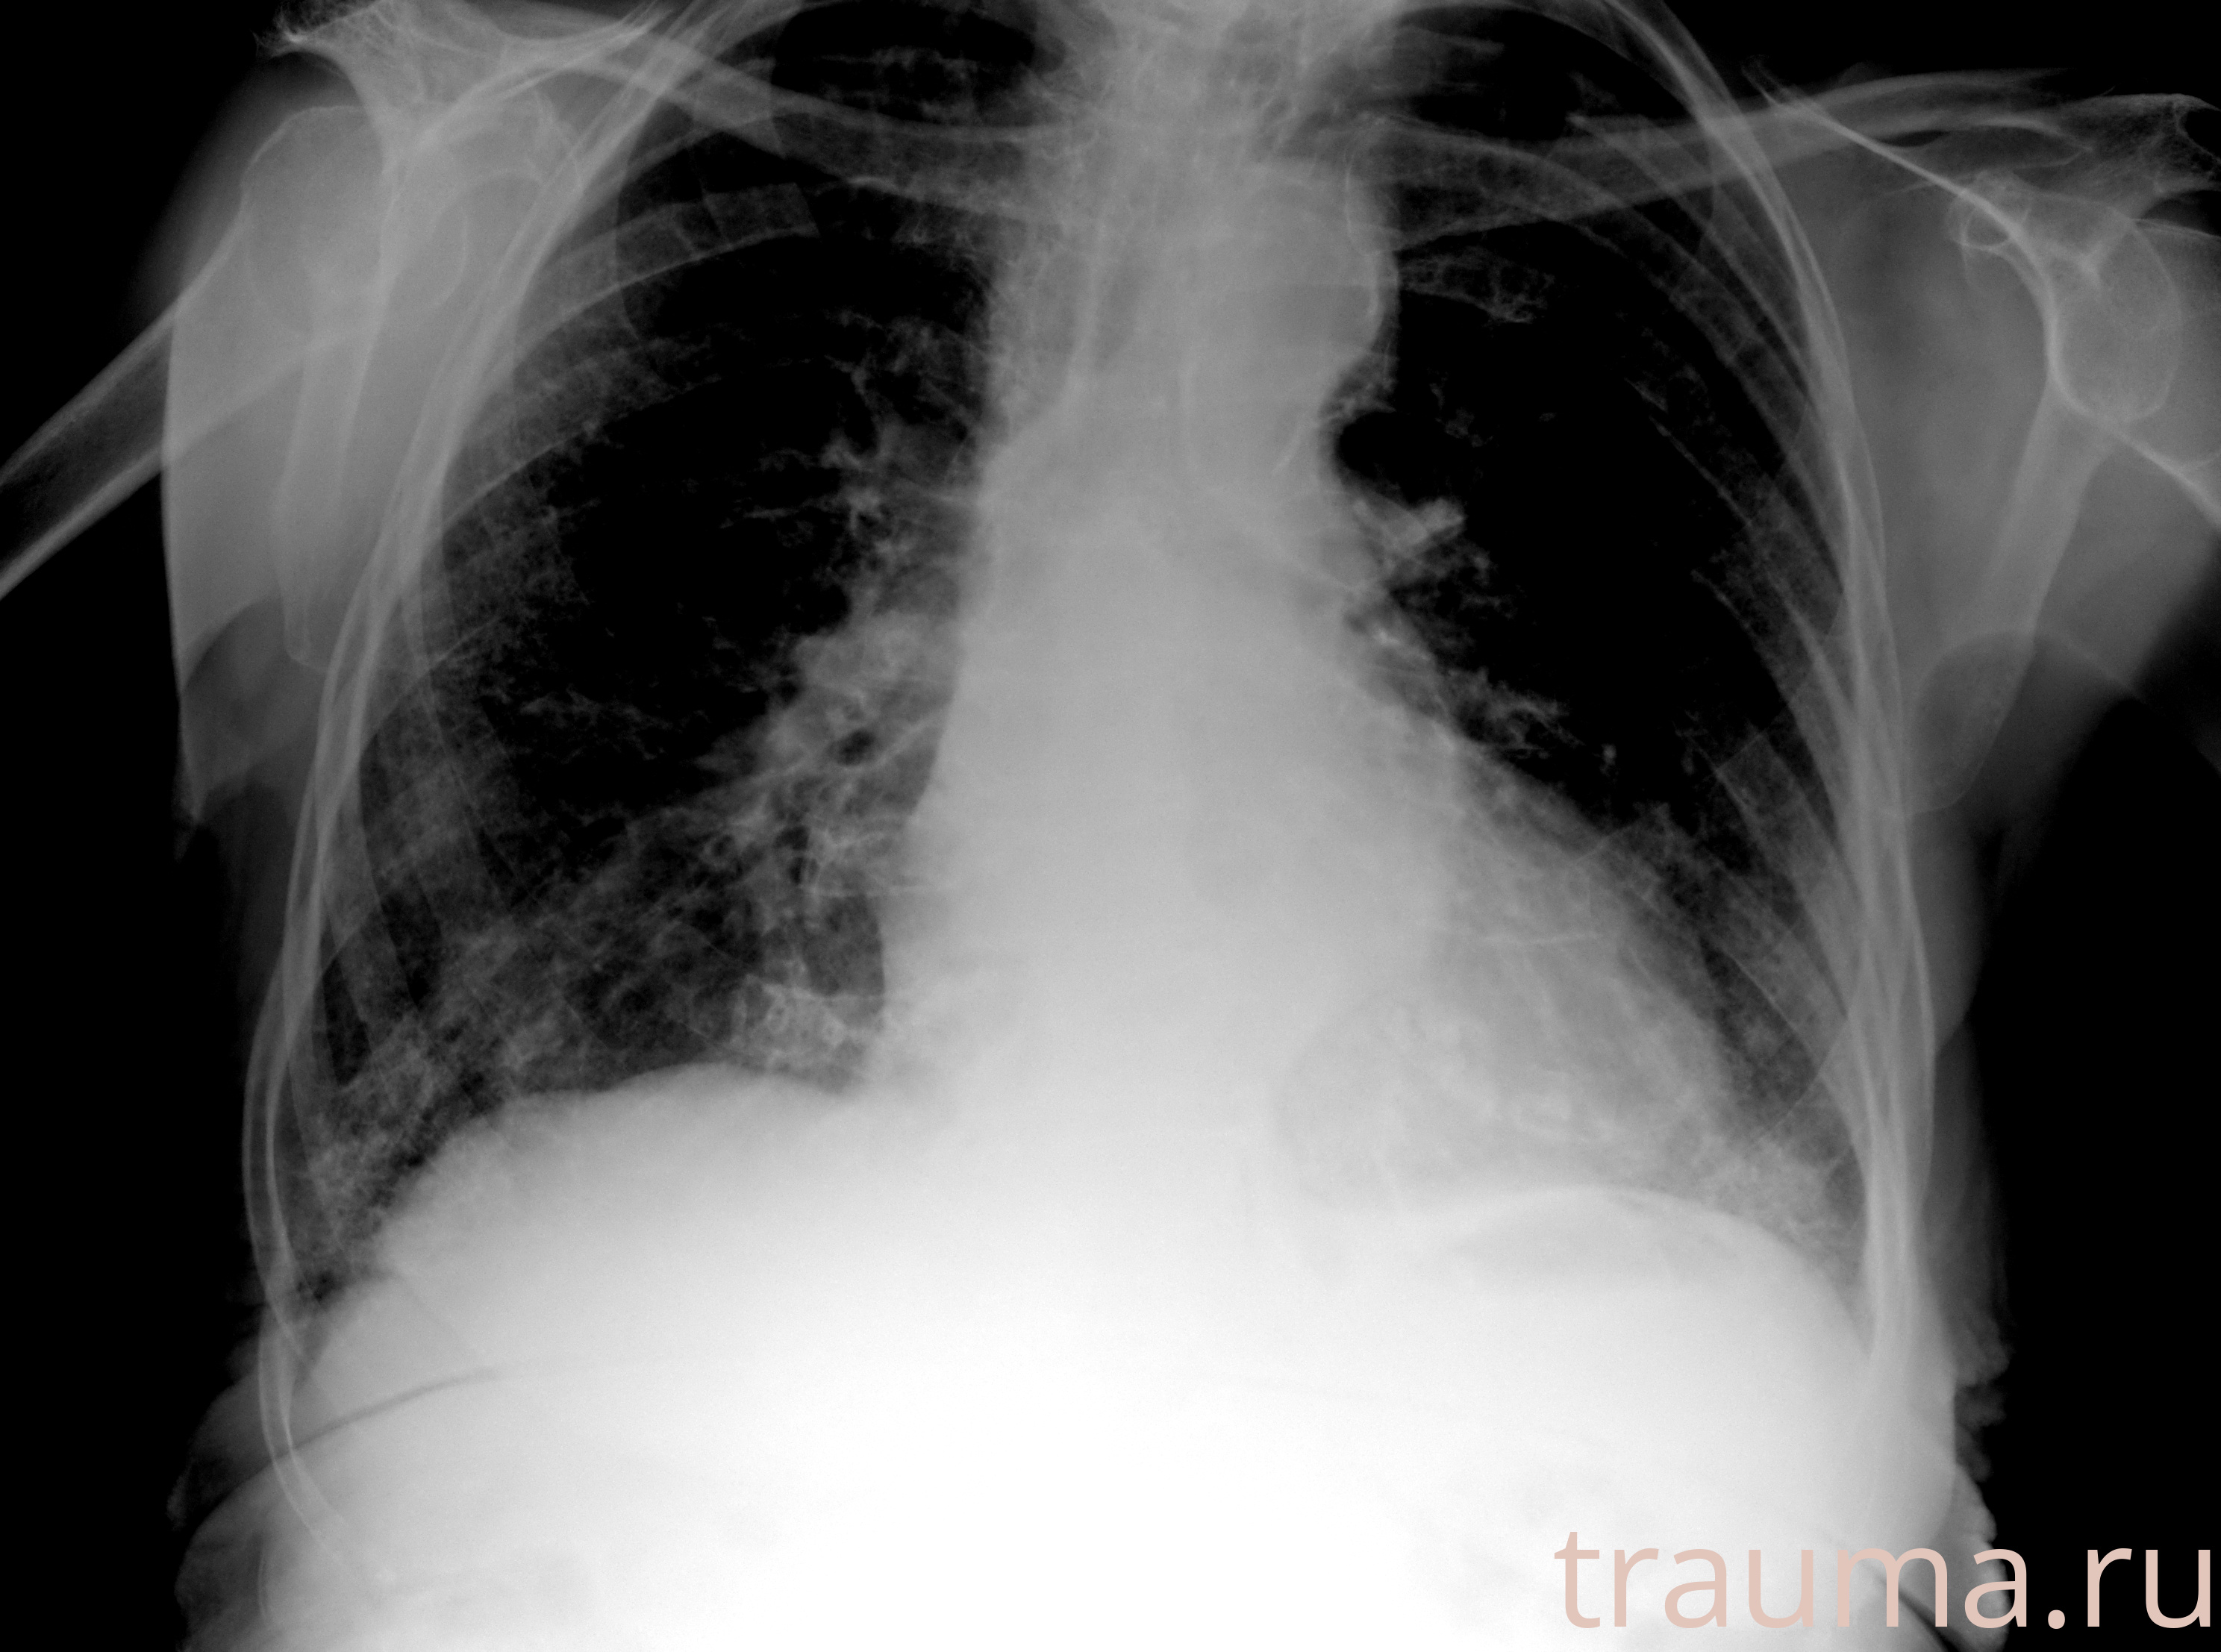

Рентгенограммы

Рентген на дому: по вашему адресу приезжает врач-рентгенолог, травматолог-ортопед с мобильным рентгеновским аппаратом, проводит диагностику травмы или заболевания, делает необходимые рентгенограммы, дает рекомендации по дальнейшему лечению. Получить качественные снимки в домашних условиях возможно благодаря уникальной методике, разработанной МосРентген Центром для института  Склифосовского